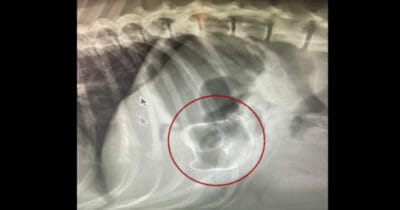

Världen över rycker brandmän ut för att hjälpa både människor och djur när de far illa. När ett gäng brandmän från Colorado Springs larmades till en plats där ett gäng valpar satt fast agerade direkt. ...